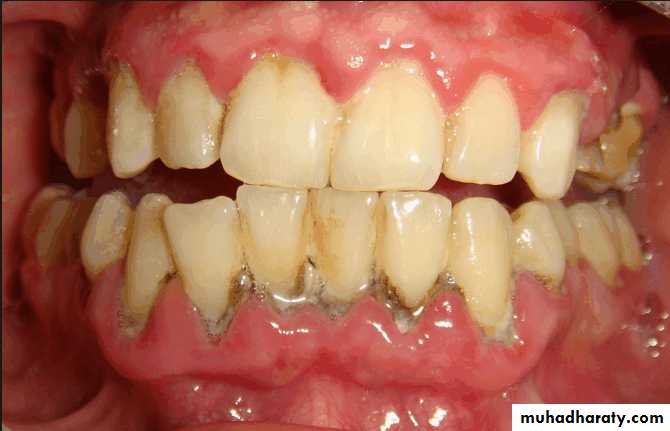

Evaluation of periodontium

Periodontal disease is one of the main etiologic factors in the loss of the teethA removable partial denture placed in the presence of active periodontal disease will contribute significantly to the rapid progression of the disease and the loss of the remaining teeth.

The causative factors must be eliminated, the disease process must be controlled before the fabrication of the prosthesis.

Examination findings that indicate possible need for periodontal treatment include

Pocket depth in excess of 3 mmFurcation involvement

Deviations from normal color and contour in gingiva, indicating gingivitisMarginal exudate

Potential abutment teeth with less than 2 mm of attached gingiva

Pulling of muscle or frena on attached gingiva